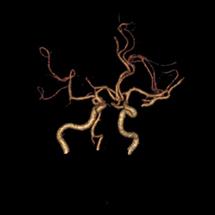

脑动脉开窗畸形通常在尸检或者影像学检查时被发现。CTA和MRA不仅能够无创地显示开窗畸形的位置、形态和毗邻结构,还能显示伴发的其它病变,是脑动脉开窗畸形2种最佳的诊断方法。当脑动脉开窗畸形难以跟动脉夹层进行鉴别时,可以考虑行脑血管造影检查,进行三维重建便可进一步帮助鉴别。